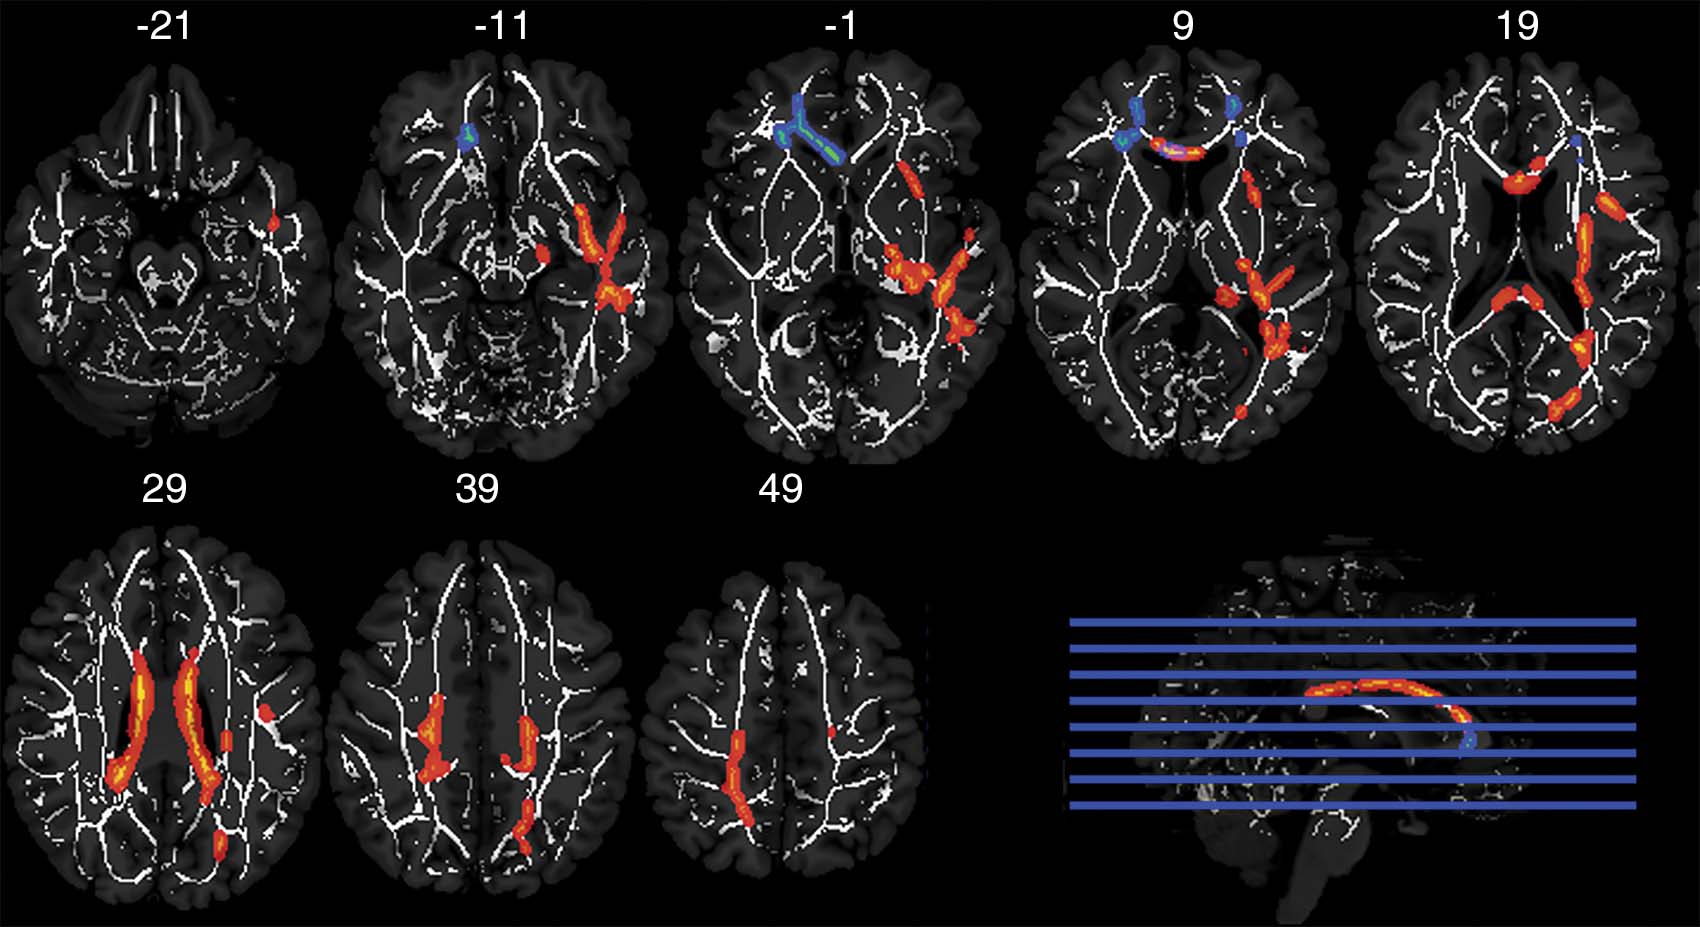

Axial MRIs

Axial MRIs show results of tract-based spatial statistics analysis of white matter fractional anisotropy clusters of voxels with a significant crossover interaction (P ˂ .05, corrected) between concussion history and career duration (red and orange) and between concussion history and playing position (blue). Clusters are overlaid on the mean white matter skeleton (white) in Montreal Neuroimaging Institute space (y coordinates are shown in millimeters).